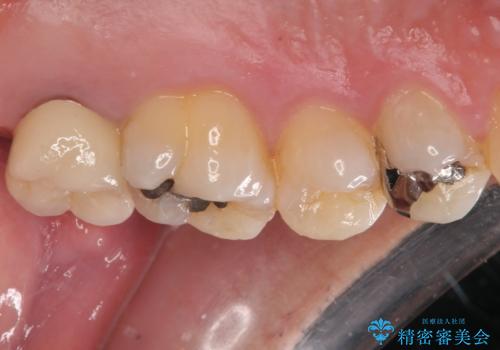

骨の透過像が非常に大きく、根管も大きく削られていたため、歯根破折による抜歯の可能性がありましたが、根管治療可能な状態でした。

初回治療後には速やかに痛みが改善され、非常に大きかったレントゲンでの骨透過像も改善されました。